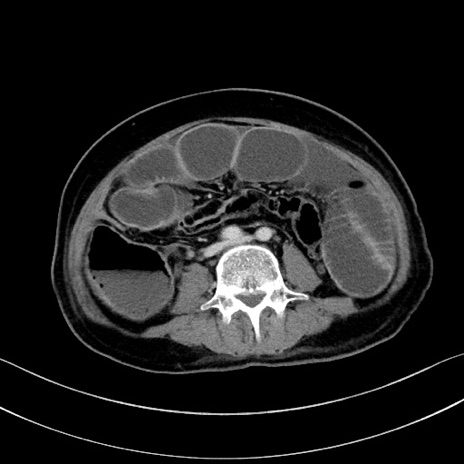

症例28(横断像)

【症例】60歳代男性

【現病歴】胃癌にて胃全摘後。食思不振が悪化し、夜中に嘔吐することがある。

【既往歴】胃癌、胃全摘、脾摘、胆摘後